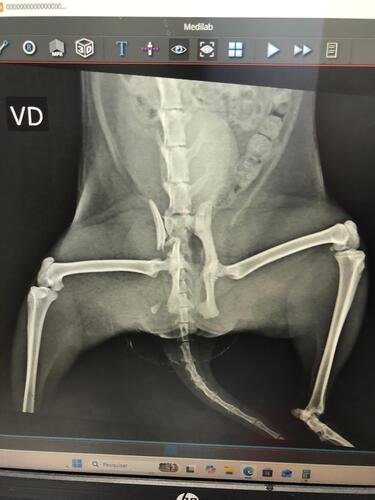

Olá, meu nome é Gigi! Tenho 2 anos e sou uma gatinha muito amorosa. Aconteceu uma coisa muito triste comigo: furei a grade da varanda e caí do quarto andar da minha casinha. Fraturei um osso e estou com muitas dores. Minha mamãe humana está correndo comigo desde quarta-feira, dia 25 de março de 2026, em um hospital público, mas eles não fazem esse tipo de operação que eu preciso. No hospital particular, ficou muito caro. O mais barato que encontraram foi:

- Raio x e Ultrasonografia: R$ 258,00